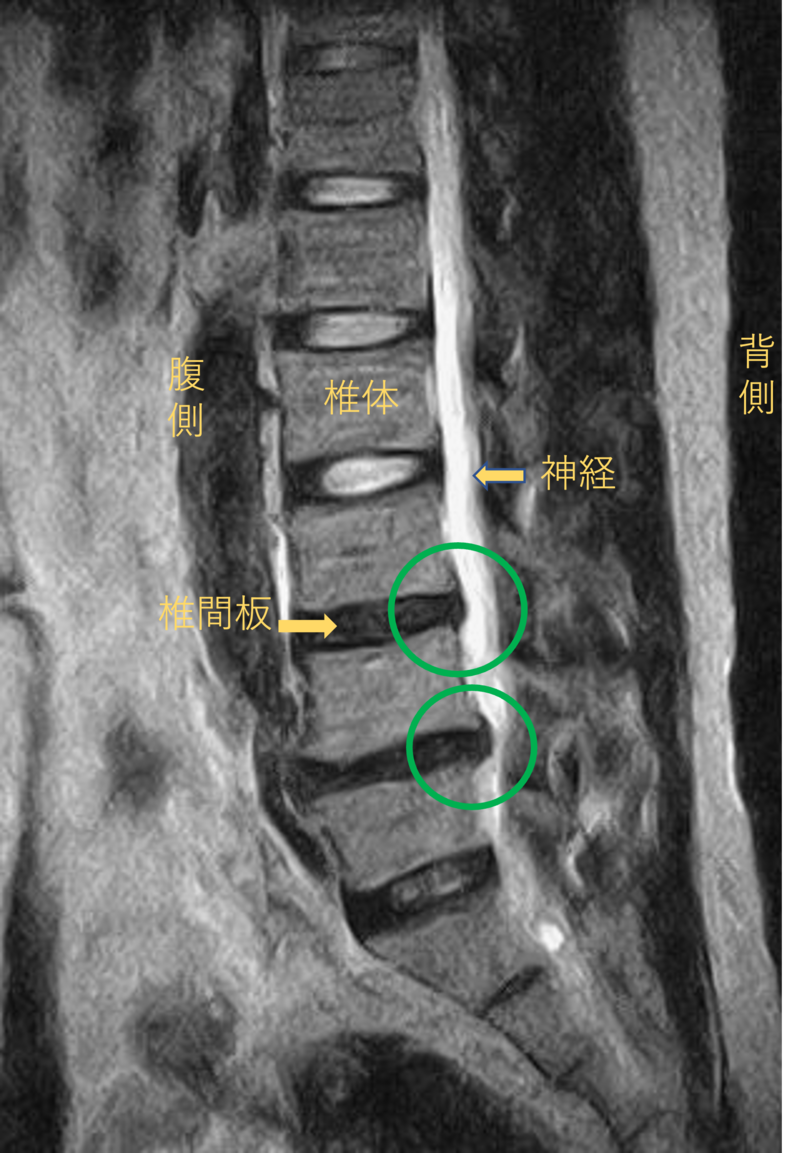

腰を横から見たMRI画像です。

腰椎という骨と骨の間に椎間板と呼ばれるクッションがあります。

このクッションの中身が飛び出す状態が椎間板ヘルニアと呼ばれます。

このMRI画像では、椎間板が背中側に飛び出して足に向かう神経が圧迫されることが痛み、しびれの原因となっておりました。